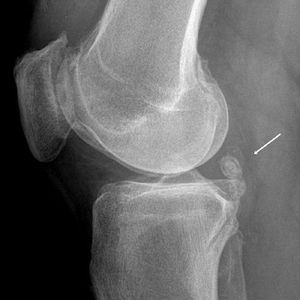

Диагностика суставной мыши осуществляется с помощью дополнительных методов обследования, среди которых наиболее важным является рентгенография. Лишь в случае значительных размеров образования его можно прощупать.

На рентгеновских снимках видно количество и форму отростков. Однако у этого метода есть серьезный недостаток: некоторые ткани не восприимчивы к рентгеновским лучам, что затрудняет получение точных данных.